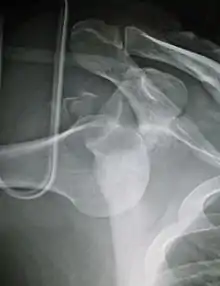

Anterior dislocation of the right shoulder. AP X ray Anterior dislocation of the right shoulder. AP X ray

Anterior dislocation of the right shoulder. Y view X ray. Anterior dislocation of the right shoulder. Y view X ray.